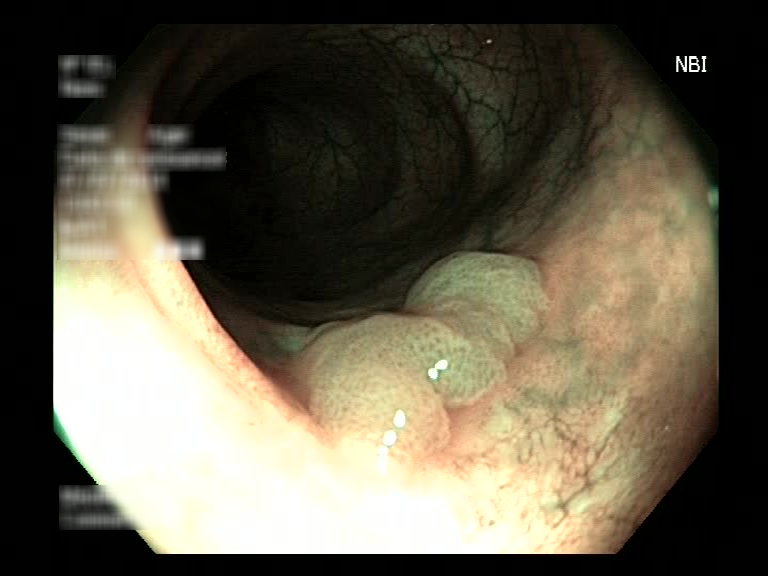

| Lesion | White Light Frame | NBI Frame | White Light Video | NBI Video | Camera Calibration |

| Lesion | White Light Frame | NBI Frame | White Light Video | NBI Video | Camera Calibration |

| serrated_01 |  |

|

WL.mp4 | NBI.mp4 | cam.xml |